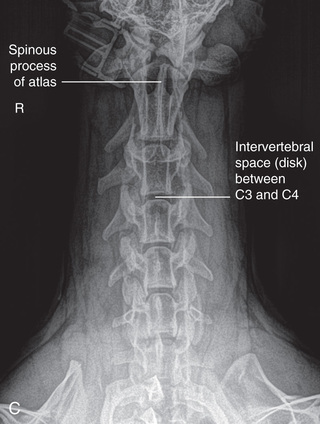

However, in spite of the limitations, proper survey vertebral radiographs are a valuable tool for those patients who have suffered spinal injuries and present with paresis or paralysis, either partial or complete. In addition, survey radiographs can demonstrate many of the signs consistent with intervertebral disk protrusion. Common intervertebral disk protrusion sites are T12 to T13, T13 to L1, C2 to C3, and C3 to C4.1

High-quality images are needed to see subtle changes in bone opacity, shape, and angulation of the vertebrae or vertebral column1,2 (Table 20.1). The common views of this portion of the axial skeleton are the lateral (L) and ventrodorsal (VD) views of the cervical, thoracic, thoracolumbar, lumbar, lumbosacral, sacral, and caudal vertebrae. Depending on the size of the patient, a full survey study is either four or five images of each orthogonal view.